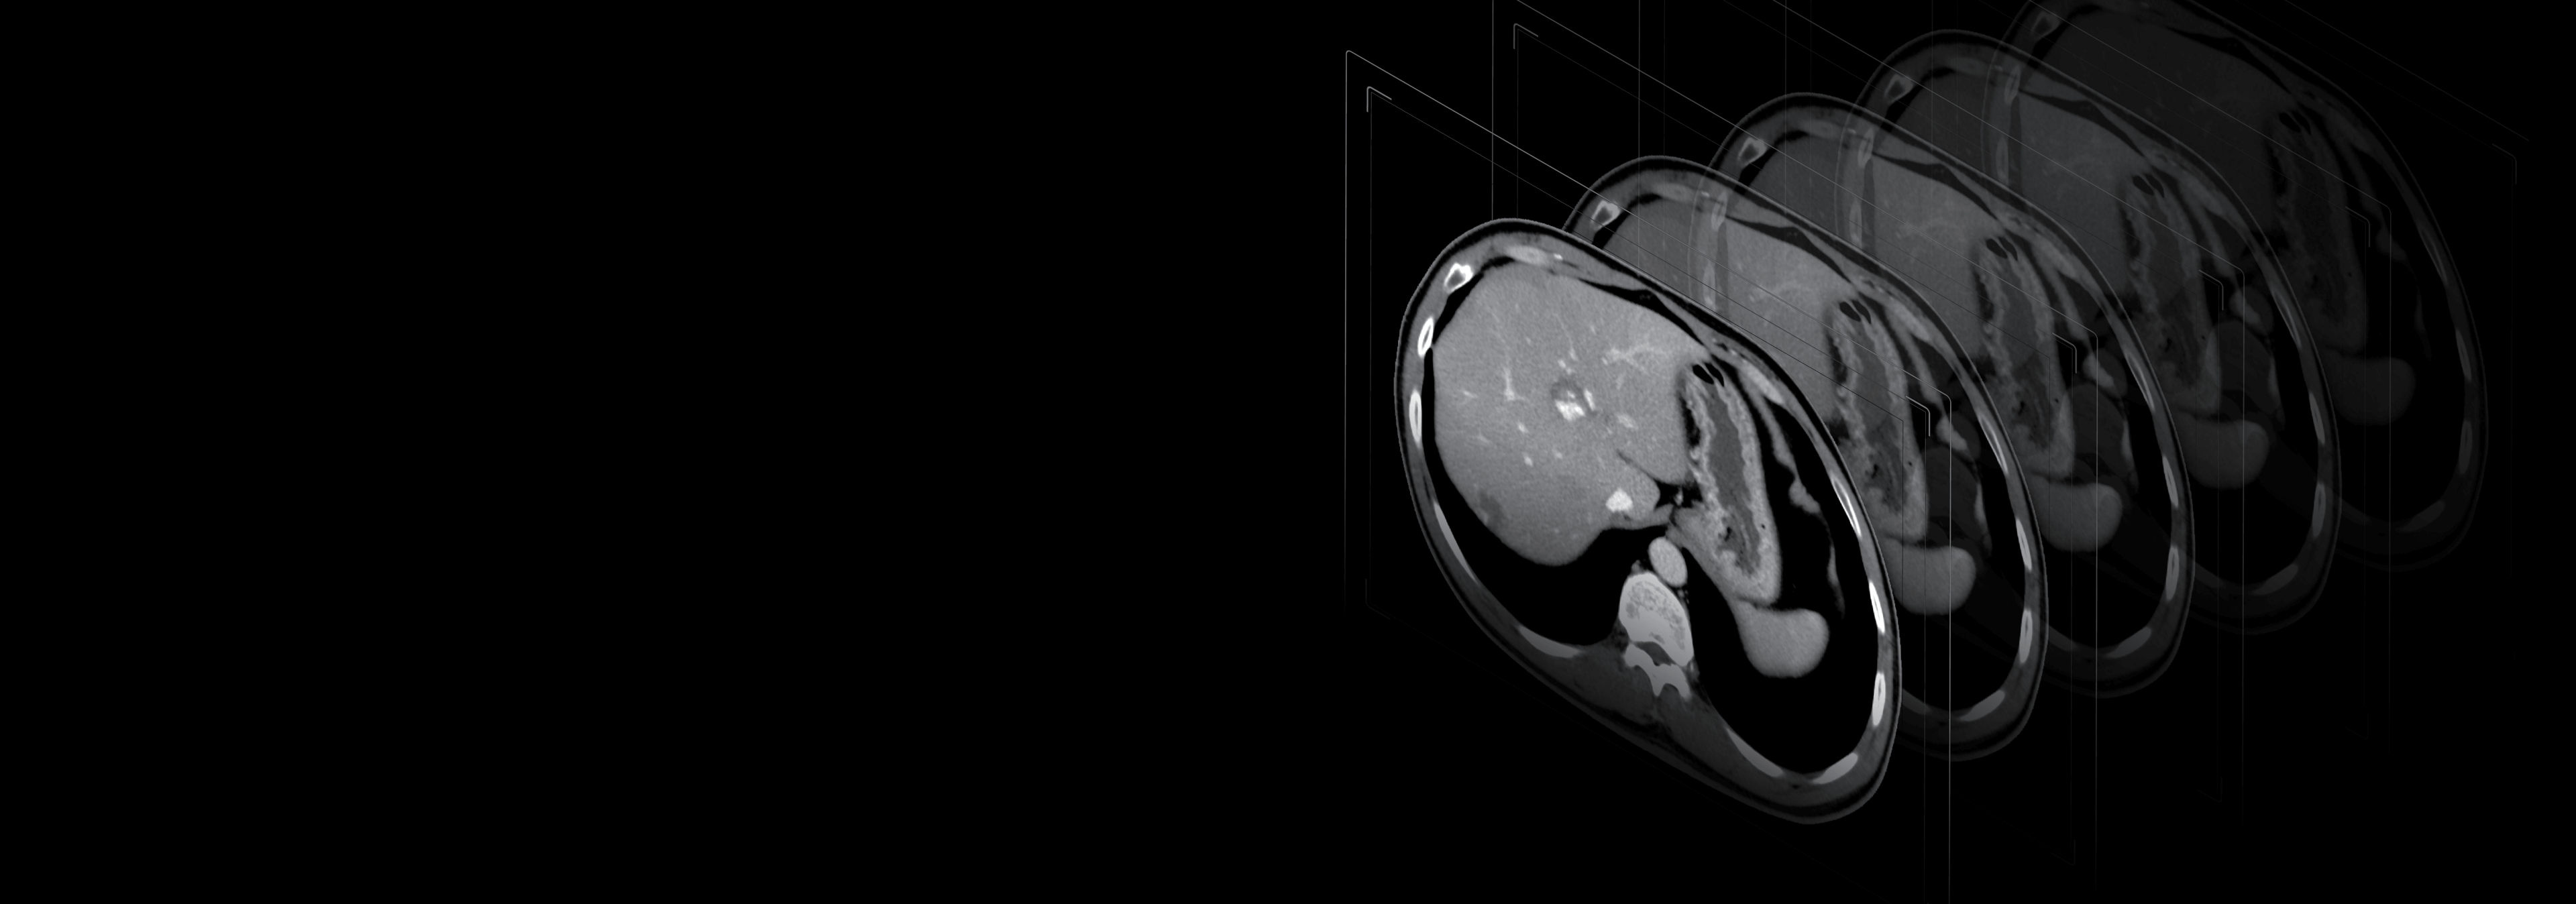

40排时空探测器

22mm覆盖,0.55mm层厚,卓越空间分辨率与密度分辨率兼而得之